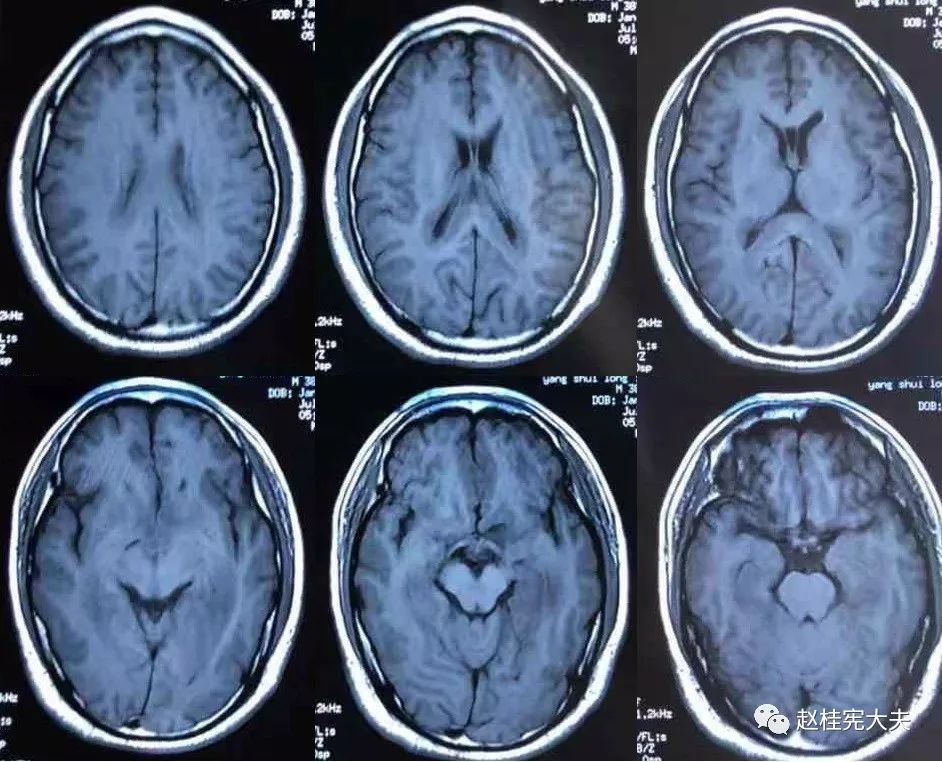

2018.7.6头颅MRI:胼胝体、穹隆及双侧脑室旁、基底节区、右侧延髓、桥臂异常信号,脱髓鞘病变考虑。头颅MRS:左枕叶病变区MRS显示:NAA下降,Cho升高,Cho/NAA=3.86,并见倒置乳酸峰。

2018.7.10磁共振增强:脑室周边病灶轻度强化。

7.20复查头颅MRI平扫:胼胝体、穹隆及双侧脑室旁、基底节区、右侧延髓、桥臂广泛信号异常,对照前片(7.10)范围明显缩小。

2018.10复查头颅MRI:胼胝体压部、左侧部分枕颞叶、侧脑室枕角旁、中脑脱髓鞘病变,视神经脊髓炎谱系病?结合对照前片(7.4)病变范围有所缩小。

我看到患者时的思考:当了解了患者前期诊疗经过后,在看到患者磁共振片子时,我的第一反应就是淋巴瘤。尽管患者激素治疗后症状有好转,病灶在磁共振上看起来也是有好转,但淋巴瘤也会出现这样的表现。

我对满脑室边的病灶的体会是:遇到这样的病例,首先要考虑感染、肿瘤(如室管膜瘤、生殖细胞瘤、淋巴瘤或转移瘤脑室播散等等),炎症要放到后面去考虑,脱髓鞘的诊断要打个大大大大的?。炎症中,血管炎不像,自免脑也不是很支持,尽管边缘系统似乎也有受累,但患者边缘叶脑炎的精神、行为异常、癫痫等症状很少,而且磁共振上看去除了边缘系统,整个脑室系统都有受累,这个和常见自免脑不符。视神经脊髓炎谱系病?尽管病灶在水通道蛋白富集区,但这样的视神经脊髓炎(视神经和脊髓均未受累,近脑室边的异常信号)至少罕见,即使诊断,也应该是排除其它的疾病后才可能考虑。